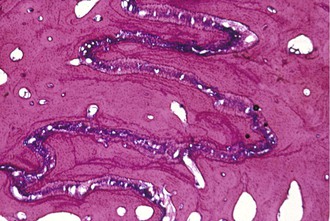

The sutural articulations in children are simple; interdigitations interlock more with age. A clear example is the midpalatal suture. The suture remains patent long after growth is complete but it becomes difficult to open with an RPE after the age of 15 to 16 years due to the complex interlocking of sutures. Conversely, in adolescents, midpalatal suture opening is very simple and can be accomplished with minimal tipping of the posterior teeth. A protraction force on the maxilla needs “disarticulation” at numerous sutures (Fig. 16-9), most notably zygomaticomaxillary, pterygopalatine, and nasomaxillary sutures of the midface. With age, these sutures become not only more mechanically intertwined, but also more tortuous in their orientation. Also, for the maxilla to advance forward in each affected suture, numerous areas of resorption and apposition must take place due to their tortuous nature, quite unlike the midpalatal suture.

Figure 16-9 Histological photograph of an area of zygomaticomaxillary suture of a Macaca nemestrina monkey subjected to an anterior protraction force. Note the tortuous nature of the suture with areas of stress and strain and resting lines.